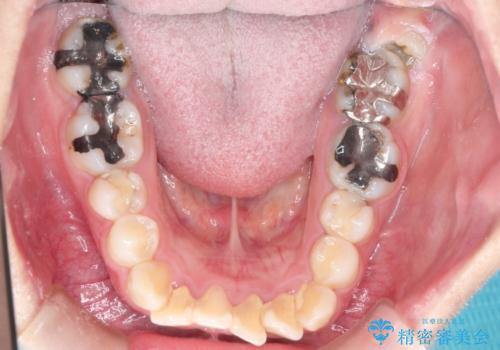

上下左右小臼歯を抜歯して審美装置で治療を行いました。

抜歯したスペースをきちんと下げることができるように、矯正用のアンカースクリューを用いて治療をしております。